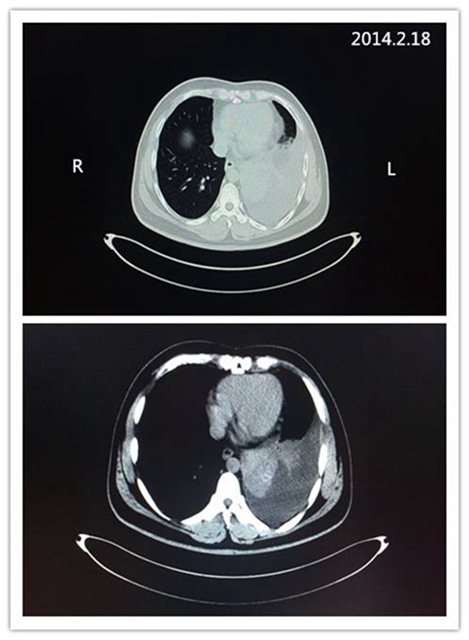

该患者接受治疗前的CT影像: